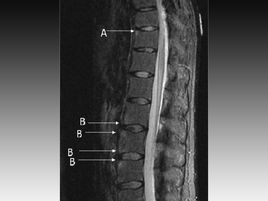

未分化脊柱關(guān)節(jié)病是指一組具有脊柱關(guān)節(jié)病的某些臨床和(或)放射學(xué)特征,而又表現(xiàn)不典型,但尚未達(dá)到已確定的任何一種脊柱關(guān)節(jié)病診斷標(biāo)準(zhǔn)的疾病。它不是一個(gè)獨(dú)立的疾病,也不是一種綜合征,它只不過是一組癥狀譜和臨床相的命名,是一個(gè)臨時(shí)診斷,借以區(qū)分類風(fēng)濕關(guān)節(jié)炎、彌漫性結(jié)締組織病以及其它風(fēng)濕性疾病。未分化脊柱關(guān)節(jié)病可以表現(xiàn)為一種或多種癥狀,可間歇出現(xiàn),可有不同輕重和不同病程。